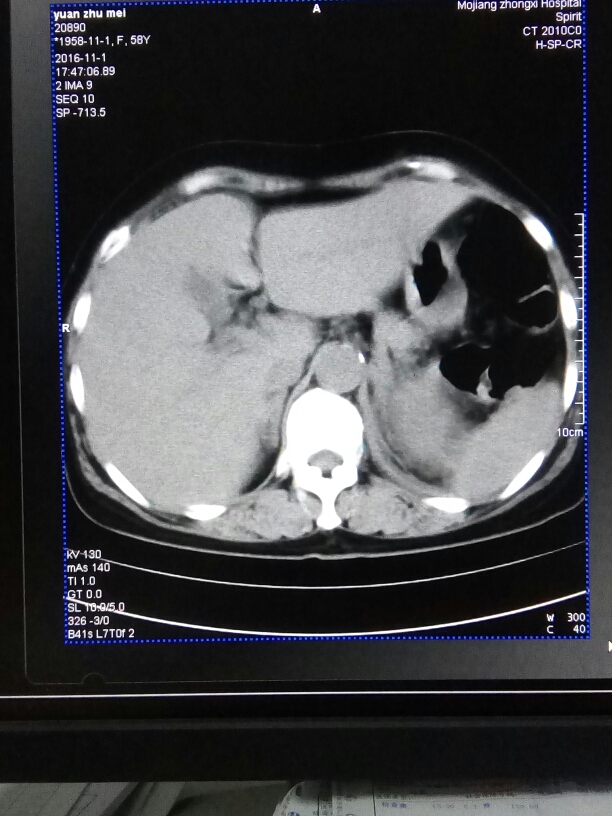

CT52335:肾

左肾是否代偿。

左肾建议增强扫描。另见胃壁明显增厚,需排除占位。

左肾代偿性增大,并旋转不良。左肾周边缘模糊,考虑感染性病变。建议核磁或增强CT。

右肾缩小。

左侧肾脏旋转不良,肾脏明显增大,内密度不均匀,肾周间隙显示不清晰,建议MR或CT增强检查

左侧肾脏旋转不良,肾脏明显增大,内密度不均匀,肾周间隙显示不清晰,考虑;感染性病变。

应该是左肾代偿,建议增强,进一步观察肾排泄功能。